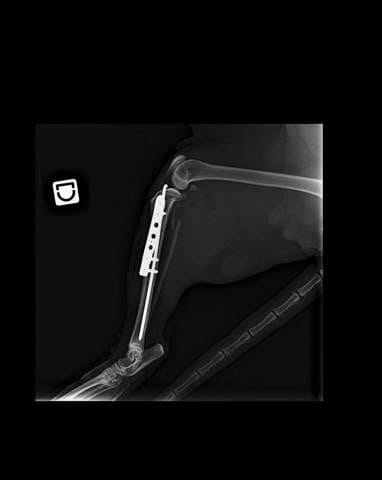

Celui-ci c'est fait percuter par une voiture et a été emmené chez le vétérinaire le plus proche.

Après avoir passé une radio, le verdict est tombé... Les deux pattes arrières sont fracturées.